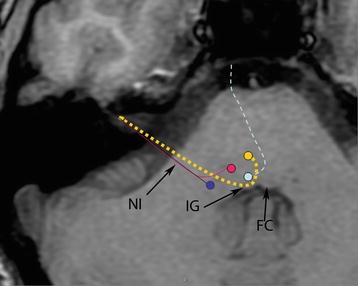

The facial nerve (the labyrinthine segment) is the seventh cranial nerve, or simply CN VII . It emerges from the pons of the brainstem, controls the muscles of facial expression . . .

The first extracranial branch to arise is the posterior auricular nerve . The first motor branch arises within the facial canal; the nerve to stapedius . [start-clinical] .

The branches of the nerve which are responsible for the various facial expressions are: 1 . Temporal branch 2 . Zygomatic branch 3 . Cervical branch 4 . Buccal branch 5 . Marginal mandibular branch .

Posterior auricular nerve, branch to posterior digastric belly, branch to stylohyoid muscle, temporal branch, zygomatic branch, buccal branch, marginal mandibular branch, cervical branch .

Branches facial nerve . Anatomy , cranial nerve , neurology , notes , practical notes . Stylohyoid supplies stylohyoid muscle . Branches in the Parotid region Temporofacial branch .